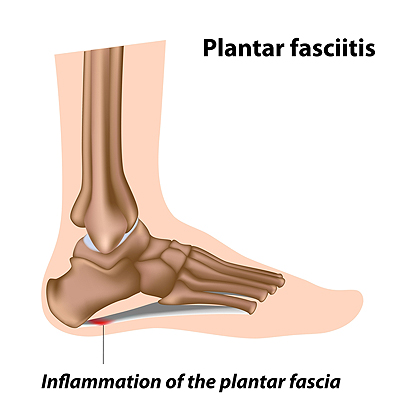

Heel Pain Causes and Treatment clearance, Heel Pain Causes Diagnosis Treatment clearance, Foot Pain Causes Treatment clearance, Plantar fasciitis treatment symptoms and causes healthdirect clearance, Plantar fasciitis Symptoms and causes Mayo Clinic clearance, Heel Pain Plantar Fasciitis is a common and Painful Condition clearance, Plantar Fasciitis Causes Symptoms Treatments and More clearance, Heel Pain causes and treatment plantar fasciitis diagnosis and treatment clearance, All About Heel Spurs Causes Treatments and Prevention Westfield Foot and Ankle LLC clearance, Plantar Fasciitis Symptoms Causes Treatment Options clearance, Plantar Fasciitis The Literal Pain In Your Heel Orthopaedic Associates of Duluth clearance, Pain in the Back of the Heel Causes and Treatment clearance, Heel Pain Types Symptoms Causes and Treatment clearance, Heel Pain Plantar Fasciitis Complete Physio clearance, Causes of Heel Pain clearance, Patient Basics Heel Pain 2 Minute Medicine clearance, Heel Pain 4 Major Causes and how to prevent them clearance, That Pain in Your Feet May be Plantar Fasciitis clearance, Heel Pain A Step Ahead Foot and Ankle Care clearance, Suffering With Plantar Fasciitis Heel Pain Symptoms Treatment clearance, Heel Pain Treatment Foot Doctor Toronto Ontario M3H 3S3 clearance, Pinpoint Your Foot Ankle Pain OrthoNebraska clearance, Heel Fat Pad Syndrome Symptoms Causes Treatment clearance, Heel Pain Podiatrist In Sterling Heights MI Advanced Foot Ankle Wound Care clearance, Plantar Fasciitis Treatment Symptoms Causes Prevention PediFix clearance, What s Causing My Heel Pain Quick Pain Relief Performance Health clearance, Why does top my heel hurt clearance, Heel Pain Treatment Nassau County Podiatrist clearance, Plantar fasciitis Information Mount Sinai New York clearance, Causes of Heel Pain clearance, Plantar Fasciitis and Foot Pain clearance, 4 Exercises to Relieve Heel Pain Kelly L. Geoghan DPM Podiatrist clearance, Why Does My Heel Hurt Syracuse Podiatry Dr. Ryan D Amico clearance, Dealing With Foot Problems Lucky Feet Shoes Has Hundreds of Styles to Help Ease Your Foot Pain clearance, Heel Spurs Causes Solutions Diagnostic Foot Specialists clearance.